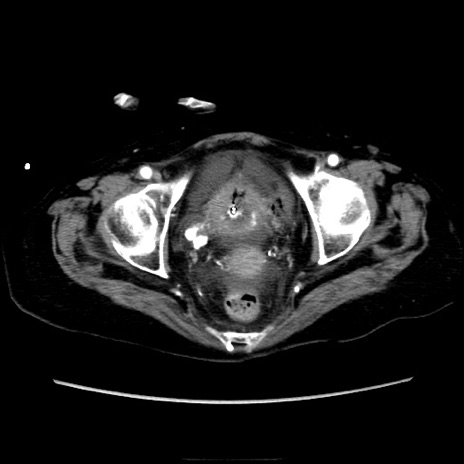

症例40(横断像)

【症例】90歳代女性

【主訴】腹痛・嘔吐

【現病歴】 食欲低下、嘔吐があり昨日他院受診。肺炎と診断され入院となる。入院後より腹部全体に圧痛あり。胃管留置され経過みていたが、症状持続するため、

当院転院となる。

【既往歴】胸椎圧迫骨折、胆石症

【身体所見】腹部:中央に激痛あり、圧痛あり、反跳痛不明

【データ】WBC 17100、CRP 18.82

横断像